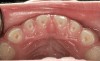

(10.) Narrow maxilla with tooth wear and bilateral crossbite.

Figure 10

(12.) Class II Angle classification with worn dentition and anterior open bite.

Figure 12